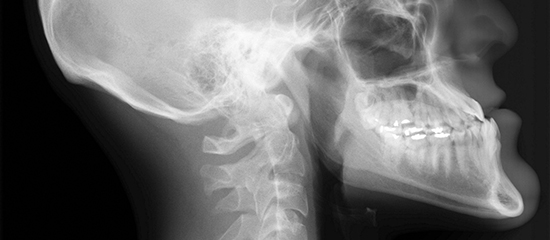

ÀÚ±âÀåÀ» ÀÌ¿ëÇØ ÀÎüÀÇ ´Ü¸éÀ» ¿µ»óÈ ÇÒ ¼ö Àִ Ư¼ö °Ë»çÀÔ´Ï´Ù. ¿µ»óÀ» º¸¸é CT¿Í À¯»çÇÏ°Ô º¸ÀÌÁö¸¸ ¹æ»ç¼±À» ÀÌ¿ëÇÏ´Â CT¿Í´Â ¾ö¿¬È÷ ´Ù¸¥ °Ë»çÀÔ´Ï´Ù. ¶§¹®¿¡ MRI°Ë»ç·Î¸¸ Áø´ÜÀÌ °¡´ÉÇÑ Áúȯµéµµ ÀÖ½À´Ï´Ù. ƯÈ÷ ³ú½Å°æ°è, ôÃß, °üÀý, ¿©¼º °ñ¹Ý Áúȯ¿¡¼ CTº¸´Ù ´õ¿í Á¤È®Çϰí À¯¿ëÇÑ °æ¿ì°¡ ¸¹½À´Ï´Ù.

| body part | °Ë»ç¸í | ÇØ´çÁúȯ |

|---|---|---|

| µÎºÎ ¹× °æºÎ | Brain, Brain MRA, Stroke study, Sella Orbit, IAC, TM joint, PNS, Neck | ³úÁ¾¾ç, ³úÃâÇ÷, ³úÁ¹Áß, ³úÇ÷°ü ÀÌ»ó, ³úÇϼöü Áúȯ, Ä¡¸Å, ¾îÁö·³Áõ, »óÇØ, °©»ó¼± Áúȯ µî |

| ÈäºÎ | Thorax, ½ÉÀå±â´É °Ë»ç, ½É±Ù°æ»ö °Ë»ç, Aorta | °¢ ºÎÀ§ ¾Ï, ½ÉÀ屸Á¶ ÀÌ»ó, ½É±Ù°æ»ö, Èä°û ±ÙÀ°, »À ÀÌ»ó, ´ëµ¿¸Æ ¹Ú¸®Áõ µî |

| º¹ºÎ ¹× °ñ¹Ý | Abdomen, Liver, Kidney, Pancreas, Pelvis, Uterus, Ovary, Hip, Others | º¹ºÎ, °ñ¹Ý, °¢ ºÎÀ§ ¾Ï(°£, ½ÅÀå, ÃéÀå, ´ã³¶, º¹¸·, ÀÚ±Ã, ³¼Ò °ñ¹Ý°, ¹æ±¤, Á÷Àå, Àü¸³¼±)À̳ª ¿°Áõ, ±¸Á¶ÀÌ»ó, °í°üÀý ÀÌ»ó, ´ëÅ𠹫Ç÷¼º ±«»ç µî |

| »çÁö ¹× °üÀý | Spine(C, T, LS), Shoulder, Elbow, Wrist, hand, Knee, Ankle, Foot | °ñÁ¾¾ç, Ãß°£ÆÇ Å»ÃâÁõ, ¿°Áõ, °üÀý Áúȯ(°üÀý¿°, ¿¬°ñ¼Õ»ó, ÀδëÆÄ¿) ±âŸ ¸ðµç °üÀý, ±ÙÀ°ÀÇ ¿Ü»ó¼º Áúȯ µî |